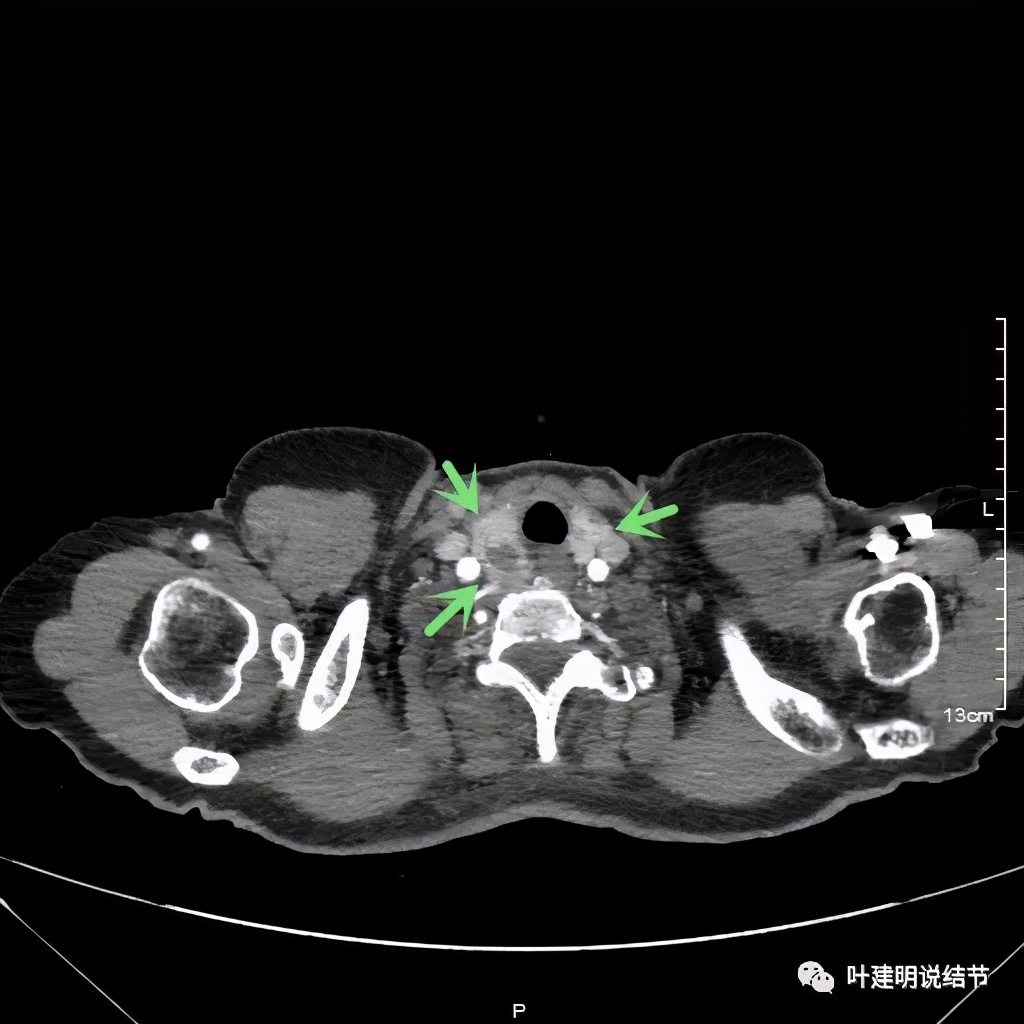

上图红色示肿瘤,黄色示气管,粉色示肿瘤与气管关系密切,桔色示左无名静脉,蓝色示上腔静脉,而且肿瘤密度不均杂乱

上图红色示肿瘤,黄色示气管,桔色示左无名静脉,蓝色示上腔静脉,而且肿瘤密度不均杂乱

上图红色示肿瘤,黄色示气管,粉色示肿瘤与气管关系密切,桔色示左无名静脉,肿瘤密度不均